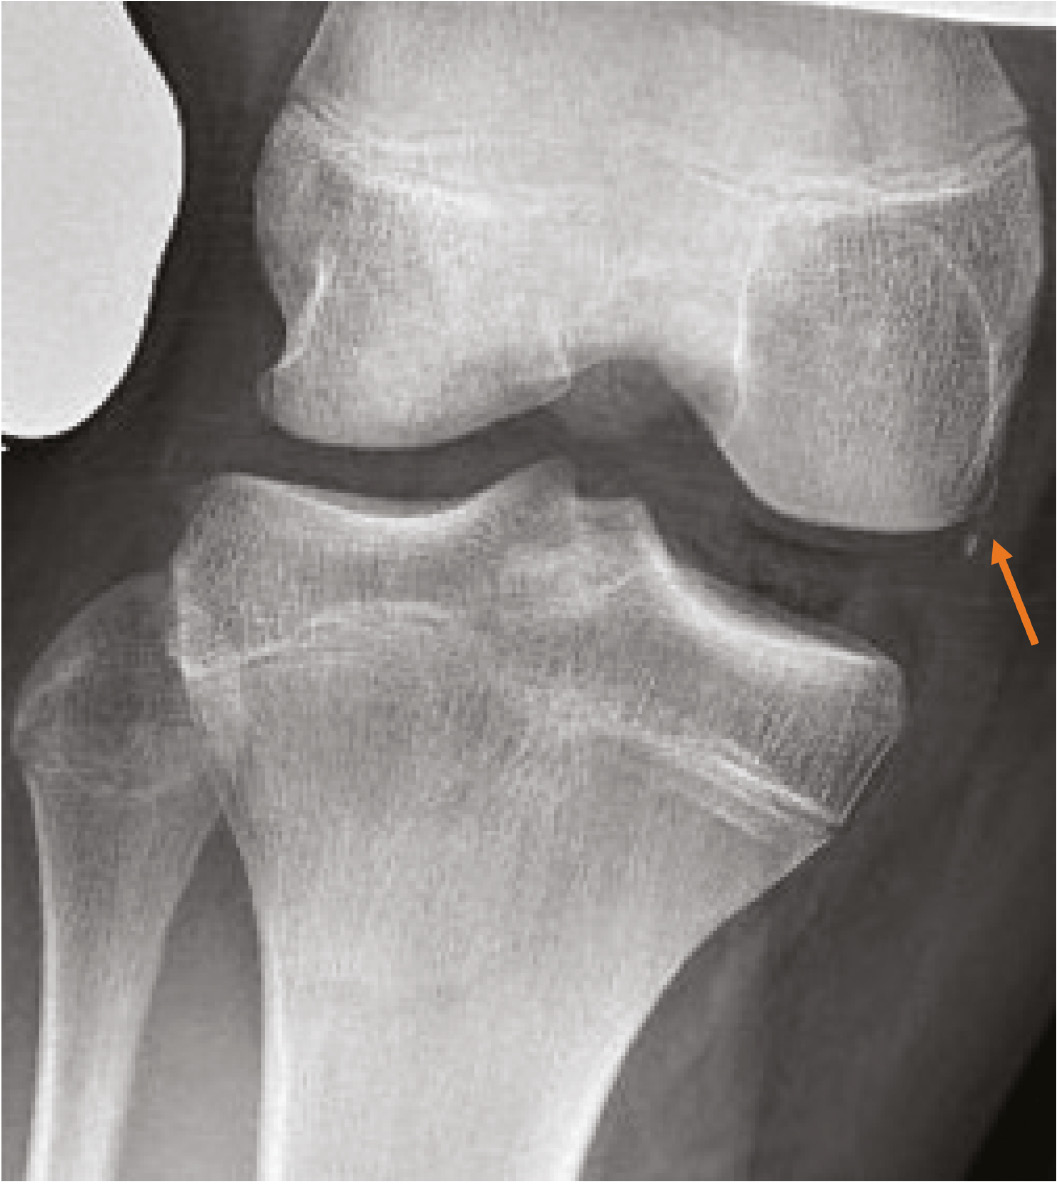

At a minimum, two radiographs (AP/lateral views) of the knee should be obtained, but a four-view series (AP/lateral/merchant/tunnel views) may be preferable to minimize the chance of missing other pathology. Examples would be a Salter-Harris III fracture of the medial femoral condyle, which represents a transitional fracture that is seen in adolescents near skeletal maturity as an alternative to an adult MCL injury (Figure 2). Additional injuries to the MCL complex include medial epicondyle fractures or fractures to the most prominent aspect of the medial condyle, bony avulsions of the deep MCL, which are frequently associated with ACL tears (Figure 3), or even the rare Salter-Harris I or II fracture of the proximal tibia in which the MCL can become interposed within the fracture (Figure 4). With longer-term follow-up, periosteal avulsions of the MCL adjacent to the medial epicondyle may result in the formation of a Pellegrini-Stieda lesion where ossification of the proximal MCL is present from either a previous avulsion of the MCL or ossification within the MCL from a chronic tear/injury pattern (Figure 5). In cases of chronic instability with suspected genu valgum, a long leg alignment film is helpful in quantifying any underlying coronal plane malalignment that may need to be corrected simultaneously or prior to a ligamentous reconstruction.

Figure 5. AP radiograph showing a Pellegrini-Stieda lesion (orange arrows) with ossification within the proximal MCL suggesting a chronic tear/injury pattern.